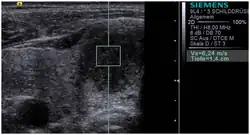

An ARFI image of a thyroid nodule in the right thyroid lobe. The shear wave speed inside the box is 6.24 m/s, which is reflective of a high stiffness. Histology revealed papillary carcinoma.

Acoustic radiation force impulse imaging (ARFI)[5] uses ultrasound to create a qualitative 2-D map of tissue stiffness. It does so by creating a 'push' inside the tissue using the acoustic radiation force from a focused ultrasound beam. The amount the tissue along the axis of the beam is pushed down is reflective of tissue stiffness; softer tissue is more easily pushed than stiffer tissue. ARFI shows a qualitative stiffness value along the axis of the pushing beam. By pushing in many different places, a map of the tissue stiffness is built up. Virtual Touch imaging quantification (VTIQ) has been successfully used to identify malignant cervical lymph nodes.[6]